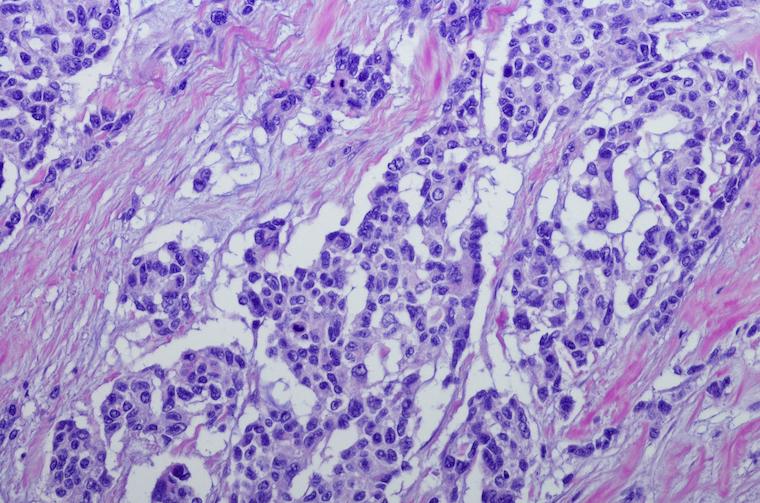

Rhabdomyosarcoma is an aggressive form of cancer that typically strikes children under 18.

The new discovery may open the door to the first targeted treatments for two types of rhabdomyosarcoma, a cancer of the soft tissue that primarily strikes young children.